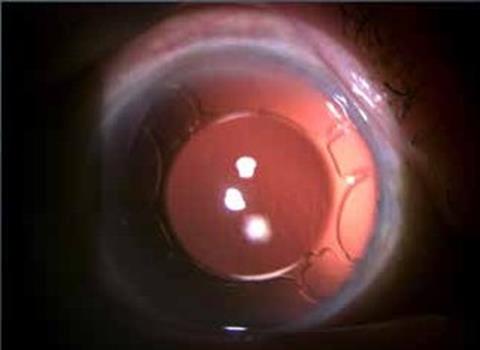

Ο ενδοφακός αυτός έχει στα δυο haptics του άγκυρες, σχήματος Τ, που επιτρέπουν τη στήριξη του ενδοφακού στον σκληρό χωρίς τη χρήση ραμμάτων, διασφαλίζοντας τη σταθερότητά του. Εκατέρωθεν των αγκυρών έχει δύο πτερύγια (flaps), που περιορίζουν την πιθανότητα κλίσης και μερικής στροφής (tilting) του φακού. Παράλληλα, το οπτικό μέρος του φακού είναι μεγάλο, 6,5mm, προσφέροντας κατάλληλη λύση ακόμα και σε περιστατικά με ανιριδία ή παραμορφωμένη κόρη, χωρίς να δημιουργεί φαινόμενα παράθλασης ή εκτροπών. Ιδιαίτερα σε περιστατικά με ανιριδία προσφέρει ελάττωση της φωτοφοβίας. Αυτό συμβαίνει διότι τα πτερύγια και τα εξαρτήματα του ενδοφακού εκατέρωθεν του οπτικού τμήματος σκεδάζουν το φως προς την περιφέρεια προστατεύοντας τον οπίσθιο πόλο από την υπερβολική έκθεση στο φως. Τέλος, το οπτικό μέρος του ενδοφακού έχει μια οπίσθια κλίση 10° που αποτρέπει την ανάπτυξη μετεγχειρητικά κορικού αποκλεισμού. Λόγω της σταθερότητας που προσφέρει ο Carlevale ενδοφακός, στο τέλος της επέμβασης μπορεί να γίνει έλεγχος της περιφέρειας του αμφιβληστροειδούς μέσω σκληρικής πίεσης, για την εύρεση και θεραπεία πιθανών ρήξεων αμφιβληστροειδούς που θα μπορούσαν να οδηγήσουν μετέπειτα σε αποκόλληση. Ως εκ τούτου οι μετεγχειρητικές επιπλοκές έχουν ελαχιστοποιηθεί, συγκριτικά με τη χρήση μη ενδεδειγμένων ενδοφακών για σκληρική στήριξη.

Κατόπιν από μία κερατική τομή των 2,75 χιλ ενθέτεται ο ενδοφακός. Απαιτείται ένα ειδικό ζεύγος λαβίδων για να μην τραυματισθούν ή αποσπασθούν οι άγκυρες του ενδοφακού κατά τη διαδικασία εξωτερίκευσής τους από τον σκληρό χιτώνα. Οι γνωστές λαβίδες του αμφιβληστροειδούς (serrated ή end- griping) συχνά τραυματίζουν ή ακόμη αποκόπτουν εντελώς την άγκυρα από το σώμα του φακού εάν ασκηθεί υπερβολική πίεση στης λαβές της λαβίδας. Υπάρχουν όμως και οι ειδικά κατασκευασμένες γι’ αυτό τον λόγο λαβίδες (Shariot και Carlevale) που έχουν μαλακές και ευαίσθητες ατραυματικές σιαγόνες. Αυτές είναι οι κατάλληλες για την τοποθέτηση του ενδοφακού. Ο φακός έχει εγκοπές στην άκρη του οπτικού του μέρους που υποδεικνύουν τη σωστή θέση του μέσα στον οπ. θάλαμο (κοίλο μέρος προς τα εμπρός). Έτσι εμποδίζεται η επαφή του φακού με το κορικό χείλος και αποτρέπεται ο κορικός αποκλεισμός και η αύξηση της ενδοφθάλμιας πίεσης. Επίσης, αποφεύγεται η επαφή και ο χρόνιος ερεθισμός της ίριδας με ό,τι αυτό συνεπάγεται.

Τέλος, εφόσον τοποθετηθεί σωστά ο φακός συρράπτεται ο επιπεφυκότας και σε κάποιες περιπτώσεις και η κερατική πύλη εισόδου του ενδοφακού για περιορισμό της μετεγχειρητικής υποτονίας. Οι χειρουργοί του υαλοειδούς μπορούν με ασφάλεια να πραγματοποιήσουν έλεγχο της περιφέρειας του αμφ/δούς για πιθανές πρΰπάρχουσες ή νεοδημιουργηθείσες ρωγμές του αμφ/δούς. Η ασφάλεια παρέχεται λόγω της σταθερότητας που προσφέρουν οι άγκυρες μέσα στο σκληρό, σε αντίθεση με όλες της άλλες τεχνικές σκληρικής στήριξης. Η απόσταση τοποθέτησης της άγκυρας από το ΣΚΟ, που είχε αρχικά προταθεί από τον Carlevale, ήταν 1,5 με 2 χιλ. Σε αυτήν την απόσταση όμως εμφανίζεται ο κίνδυνος να τραυματισθεί το ακτινωτό σώμα και να έχουμε είτε αιμορραγία είτε χρόνιο ερεθισμό που θα επιφέρει σε απώτερο χρόνο κυστικό οίδημα ωχράς κηλίδας. Ιδιαίτερα σε οφθαλμούς που έχει γίνει ολική υαλοειδεκτομή καλό θα είναι η τομή να γίνεται στα 2,5 ή ακόμη και στα 3χιλ από το ΣΚΟ (προσωπική μου επιλογή) για να ελαχιστοποιούμε την πιθανότητα των προαναφερθέντων επιπλοκών. Στις περιπτώσεις που ο φακός τοποθετείται πιο πίσω, ο υπολογισμός της δύναμης του φακού με τη βιομετρία αλλάζει. Εξαιτίας της υπερμετρωπικής εκτροπής που προκαλείται με την προς τα πίσω μετατόπιση του φακού, επιλέγεται στη βιομετρία ο φακός που να έχει απόδοση -1.00Dpt. Αυτή η διαφορά είναι αρκετή να καλύψει την υπερμετρωπική εκτροπή και να προσφέρει εμμετρωπία.

Οι αναφερθείσες-δημοσιευθείσες έως τώρα επιπλοκές είναι σαφώς λιγότερες από αυτές των άλλων τεχνικών. Η συχνότερη επιπλοκή των προηγούμενων τεχνικών ήταν η κλήση των φακών (tild) και η απώλεια με τον χρόνο της στήριξης ενός εκ των 2 σημείων στήριξης του φακού. Στους Carlevale αυτές είναι σχεδόν ανύπαρκτες. Επίσης, η πιθανότητα μετεγχειρητικής αποκόλλησης του αμφ/δους είναι μικρότερη (ιδιαίτερα σε περιστατικά με ολική υαλοειδεκτομή), διότι πραγματοποιείται στο τέλος της επέμβασης με ασφάλεια έλεγχος της περιφέρειας με σκληρική πίεση. Οπότε ανιχνεύονται προΰπάρχουσες ή πρόσφατες αμφ/κές ρωγμές και αντιμετωπίζονται αμέσως. Το κυστικό οίδημα της ωχράς κηλίδας, επίσης, αναφέρεται σε μικρότερα ποσοστά.